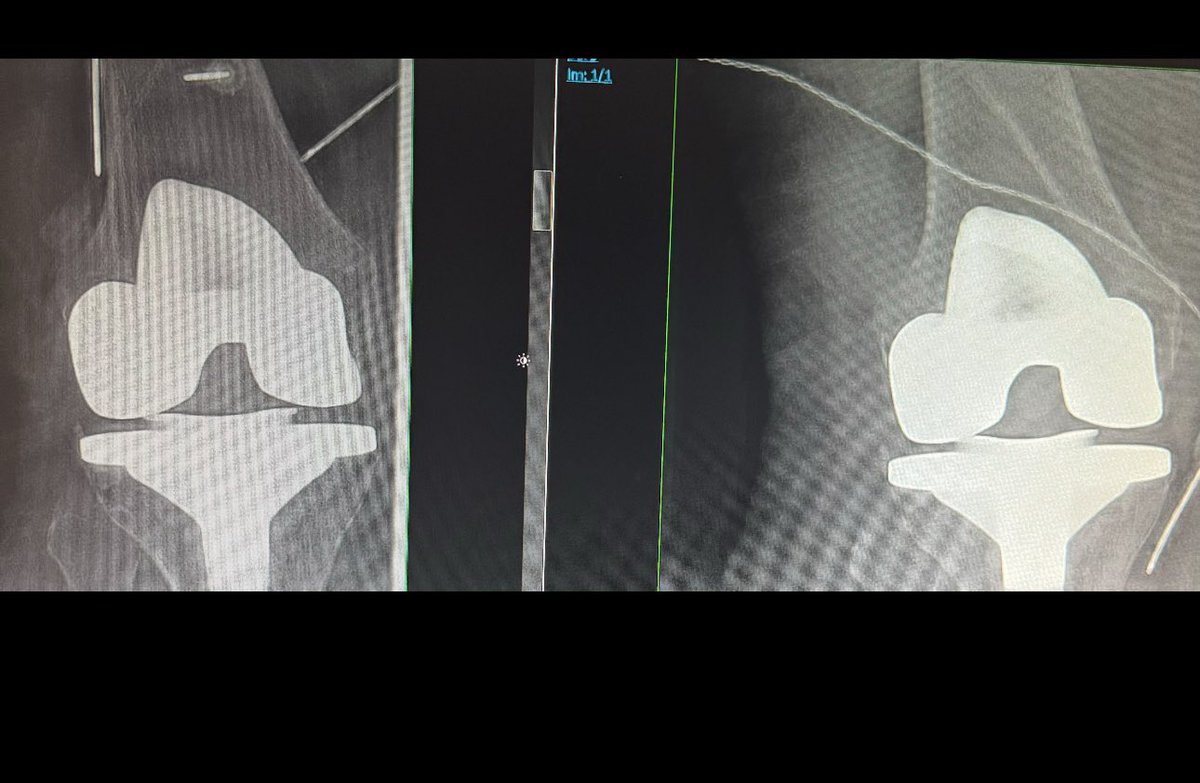

كي الاعصاب الحسيّة لمفصل الركبة بعد اجراء عملية تبديل المفصل قد يكون احد الحلول لبعض المرضى الذين لا يتحسن الالم لديهم حتى بعد اجراء عملية تبديل المفصل. فخيار كي الاعصاب الحسّية بالتردد الحراري للركبة او غيرها من المفاصل له دواعي معروفه لدى الطبيب المعالج وقد تكون خيار اولي في